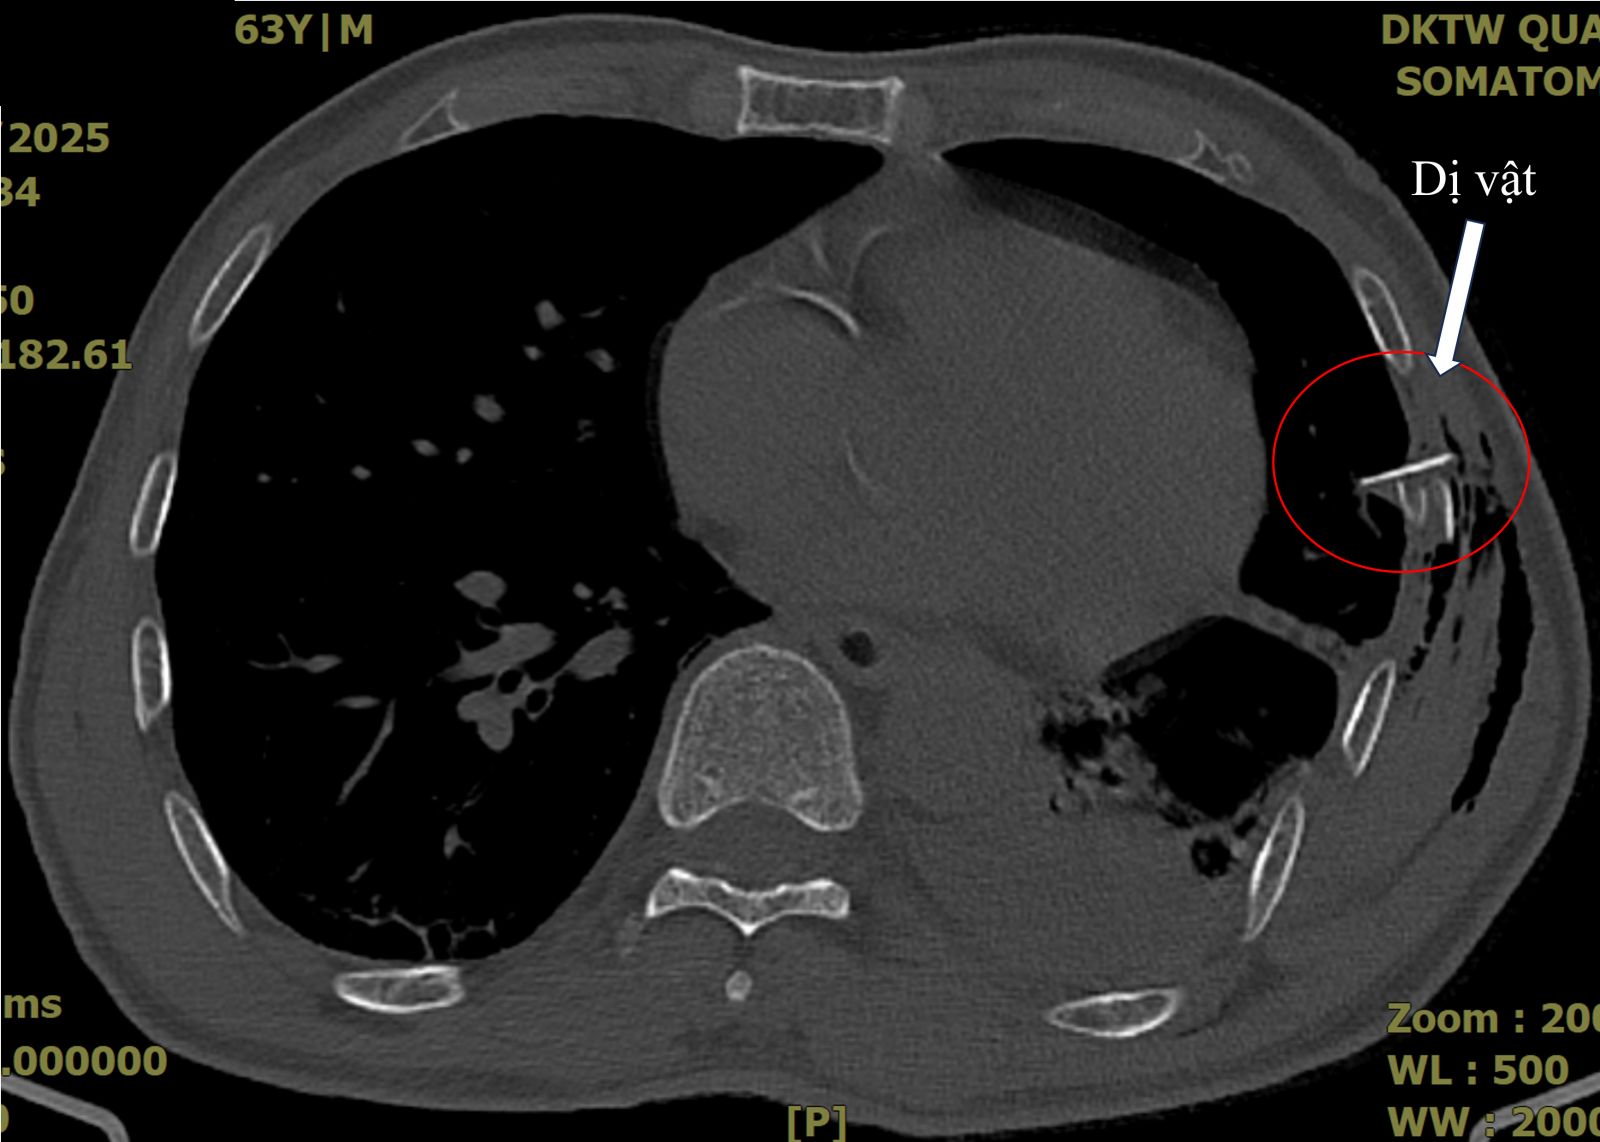

Hình ảnh chụp cắt lớp ngực của bệnh nhân V.Đ.Q. ghi nhận tràn khí, tràn máu màng phổi với một mảnh xương sườn đâm vào nhu mô phổi.

Sau đó, bệnh nhân có cơn đau ngực tăng dần, đau không dám thở, trong tình trạng suy hô hấp, hình ảnh X-quang phổi chưa ghi nhận bất thường khác ngoài gãy các xương sườn VI, VII, VII. Bệnh nhân được chụp cắt lớp ngực và ghi nhận tràn khí, tràn máu màng phổi với một hình ảnh mảnh xương sườn đâm vào nhu mô phổi.